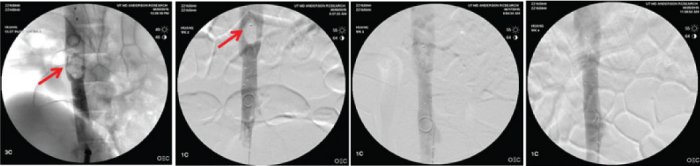

Fluoroscopic images of the absorbable (left) and control metal IVC filter (right) demonstrating filter perforation of the IVC.

Further, a randomized controlled study conducted at Synchrony Labs revealed that the absorbable filter was as effective as a leading metal IVC filter in preventing pulmonary embolism, yet was significantly safer (no vessel perforation).